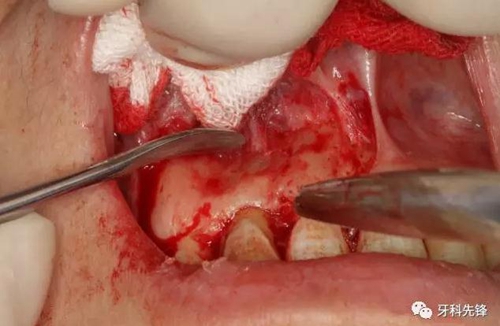

圖5.唇側(cè)梯形切口。

圖6.翻瓣、暴露術(shù)區(qū)、唇側(cè)骨板未破壞。

圖7.唇側(cè)骨板完整無缺。